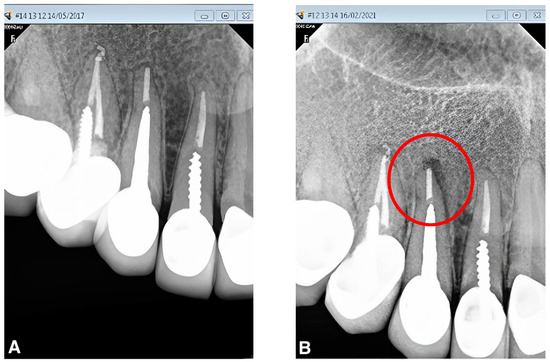

A healthy periapex PAI 1 was described as a healthy periapex, which had the normal width of permanent ligament space and surrounding bone that looked normal. The evaluation of all other PAI scores (2,3,4,5) was mentioned as apical periodontitis. The chi-square test was employed for statistical analysis, with a significance level of p < 0.05. Out of 70 recalled patients, the male students had performed a total of 20 post and core treatments, whereas the female undergraduate students had completed post and core treatments for 50 cases. A total of 90% (n = 18) of the teeth in group I with no gap between the residual gutta-percha and the post were found to be healthy, while 10% (n = 2) were found to be diseased (Figure 1). In group II, there were 66.7% (n = 22) of normal teeth and 33.3% (n = 11) of diseased teeth, with a gap of more than 0 mm to less than 1 mm between the post end and the remaining gutta-percha (Figure 2). However, 58.8% (n = 10) of group III patients with a gap of more than 1 mm between the post end and the remaining gutta-percha were found to be healthy, whereas 41.2% (n = 7) were found to be diseased. (Figure 3). A total of 32% (n = 16) endodontically treated teeth were found diseased and treated by the female students while 68% (n = 34) of teeth were found normal. A total of 20% (n = 4) endodontically treated teeth were found diseased and treated by the male students while 80% (n = 16) of teeth were found normal. (Figure 4 and Figure 5) The quadrant wise treated teeth included for follow up examinations were 36 maxillary anteriors, 8 maxillary posteriors, 12 mandibular anteriors, and 14 mandibular posteriors. Among the maxillary anteriors, 69.4% (n = 25) of teeth were found normal however 30.6% (n = 11) of teeth were found diseased. Among the maxillary posteriors, 50% (n = 4) of teeth were found normal however 50% (n = 4) of teeth were found diseased. Among the mandibular anteriors, 83.3% (n = 10) of teeth were found normal however 16.7% (n = 2) of teeth were found diseased. Among the mandibular posteriors, 78.6% (n = 11) of teeth were found normal however 21.4% (n = 3) of teeth were found diseased. (Figure 4 and Figure 5).

Figure 1. (A,B). Peri-apical radiograph in Group I (no gap between cemented post and remaining gutta-percha) showing the PAI status, before and after 4 years of follow up using the CS-R4 program.